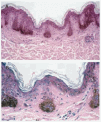

En los tres casos se realizó extirpación quirúrgica de las lesiones. El estudio histopatológico demostró una epidermis lentiginosa con hiperpigmentación de los extremos inferiores de sus crestas, escasa pigmentación de la epidermis recubriendo las papilas dérmicas, y sin aumento llamativo del número de los melanocitos (fig. 4), estableciéndose así el diagnóstico de lentigo negro reticulado.

Fig. 4.--Características histopatológicas del lentigo negro reticulado. A: epidermis lentiginosa. B: hiperpigmentación del extremo inferior de las crestas epidérmicas con escaso pigmento melánico en la epidermis entre crestas. No se observa incremento en el número de melanocitos.